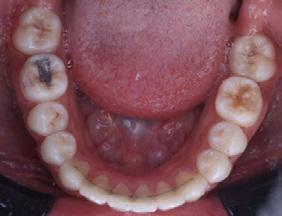

Se presenta un paciente de 29 años de edad. Al interrogatorio clínico refiere no tener alteraciones sistémicas y que actualmente no está tomando ningun medicamento, acude a la consulta odontológica para que le realisen una limpieza. En la revision clínica se observa la presencia de bioplaca y con sarro en los organos dentarios (OD) del 32 y 42 por la superficie vestibular. Por lo que se indica una profilaxis, se procedió de la siguiente manera, tinción de la bioplaca (Figura 1), realizándose el levenatmiento del índice epidemiológico IHOS. Se obtuvo el promedio de

Figura 1. Frente de inicio.

Figura 2. Vista lingual inferior dientes con sarro.

la bioplaca, el cual fue bajo según el IHOS 0.6 y el sarro se localizó en los OD Inferiores 32 y 42 por las superficies vestibular y lingual.

En la Figura 2 se ven los organos dentarios del 32 al 42 con sarro en la superficie lingual abarcando menos del tercio medio.